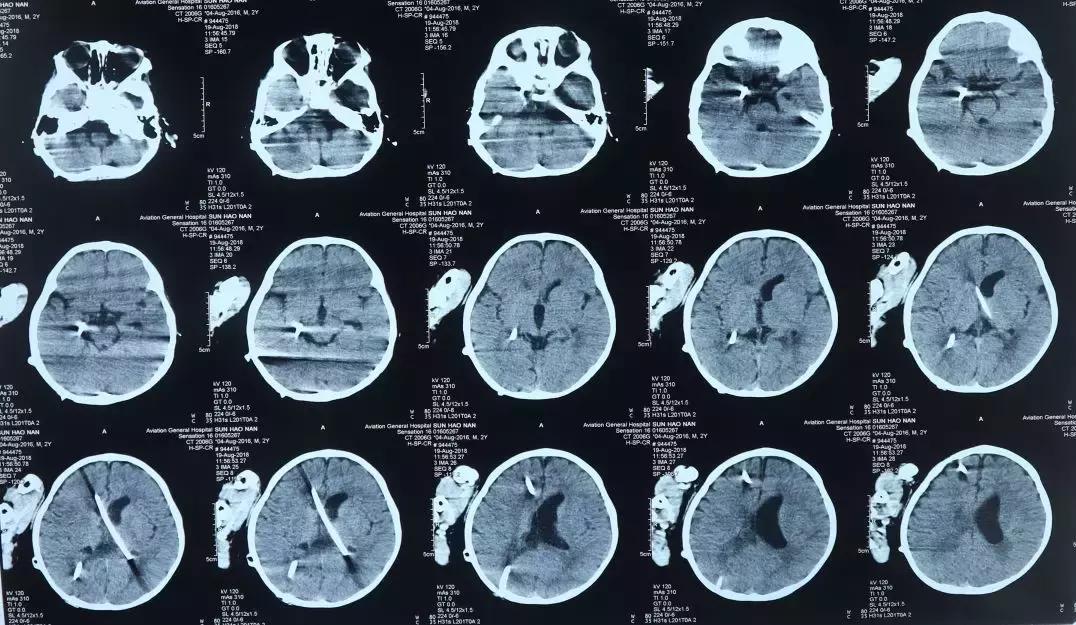

2018年8月19日复查头部影像